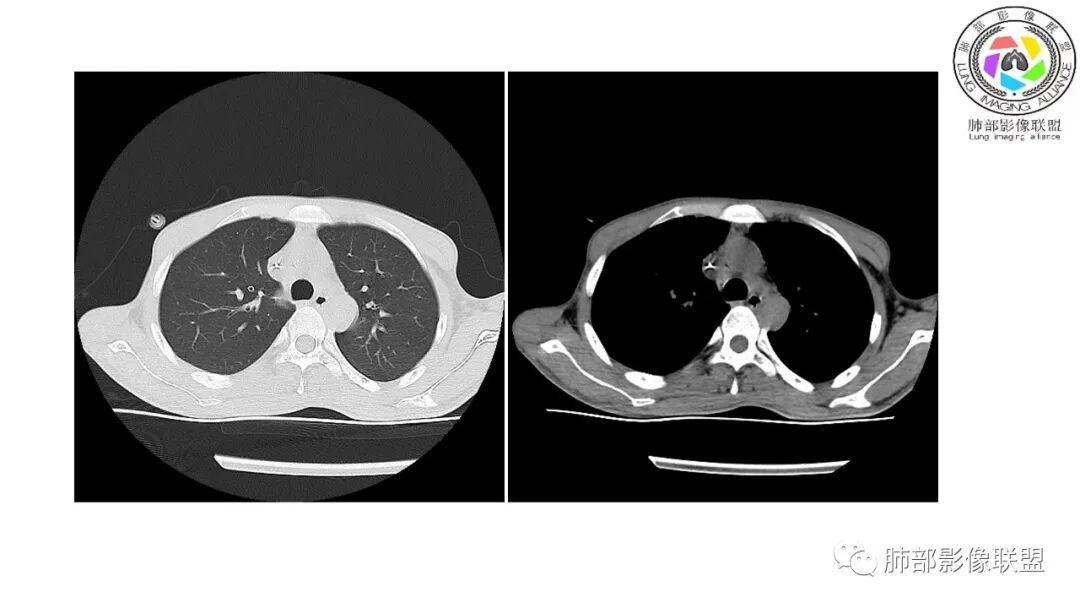

影像与临床:1.青年男性,HlV阳性,颜面部皮疹(未提供皮疹图像)、发热(高热),实验室CRP、PCT高,T-Spot阴性。2.右肺下叶空洞结节,壁厚不均,边界清楚,其内线状影,未见液平及钙化,未见卫星灶,纵隔淋巴结增大,双侧腋窝见增大淋巴结。心腔内低密度提示贫血可能。肝脾影增大,未见结节影及块影。腹膜后见多发增大淋巴结。

综合分析:本例肺部影像学改变并不具有特征性,空洞性病灶须与多种疾病鉴别,但年轻HIV阳性患者,高热,皮疹,肝脾增大,纵隔、腋窝、腹膜后见多发增大淋巴结等都强烈提示马尔尼菲篮状菌感染的可能性。